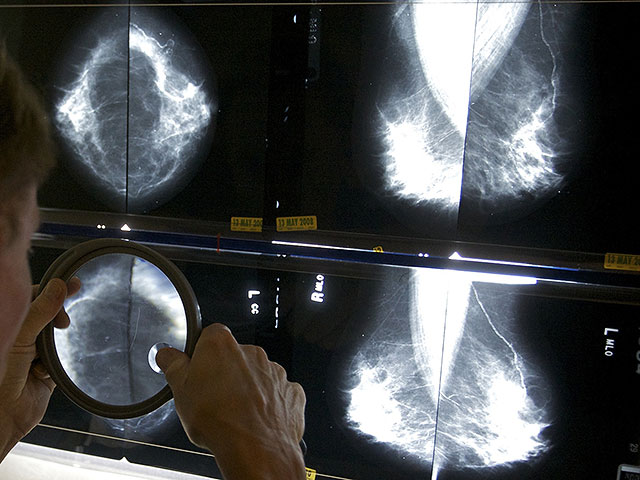

Модель ИИ, использующая изображения маммографии для оценки пятилетнего риска развития рака молочной железы, продемонстрировала более точное и надежное распределение женщин по группам риска по сравнению с традиционной оценкой плотности молочной железы. К таким выводам пришли исследователи в новом исследовании, которое представят на ежегодной конференции Радиологического общества Северной Америки (RSNA).

Clairity Breast – первая одобренная FDA ИИ-система для прогнозирования риска рака молочной железы, работающая исключительно на основе маммографических снимков. Она была обучена на массиве из 421 499 маммограмм, полученных в 27 медицинских учреждениях Европы, Южной Америки и США. В обучение включили как снимки женщин, у которых впоследствии был обнаружен рак, так и тех, у кого он не развился в течение пяти лет. Это позволило ИИ выявить особенности структуры тканей, связанные с будущим возникновением заболевания. Для формирования пятилетних прогнозов риска модель была откалибрована на независимом наборе данных с использованием глубокой сверточной нейронной сети.

Затем модель применили к большой когорте – 236 422 двухсторонним скрининговым 2D-маммограммам из пяти медицинских центров США и 8 810 маммограммам из клиники в Европе, полученным в 2011-2017 годах. Данные о категории плотности молочной железы и информация о диагнозах рака за пятилетний период были взяты из медицинских карт и онкологических реестров. Прогнозы ИИ распределяли по уровням риска в соответствии с порогами Национальной комплексной онкологической сети: низкий (менее 1,7%), промежуточный (1,7-3,0%) и высокий (более 3,0%). Анализ проводили с помощью статистических моделей, учитывающих длительность наблюдения и случаи цензурирования.

Даже с учетом плотности молочной железы выявлено, что у женщин, отнесенных ИИ к группе высокого риска, рак возникал более чем в четыре раза чаще, чем у женщин со средним риском (5,9% против 1,3%). В то время как сама по себе плотность груди демонстрировала лишь небольшие различия в заболеваемости – 3,2% у женщин с плотной тканью и 2,7% у женщин с неплотной.

Эти результаты показывают, что ИИ-модели риска значительно превосходят традиционные подходы, основанные только на плотности молочной железы, обеспечивая более точное прогнозирование риска развития рака в течение ближайших пяти лет.